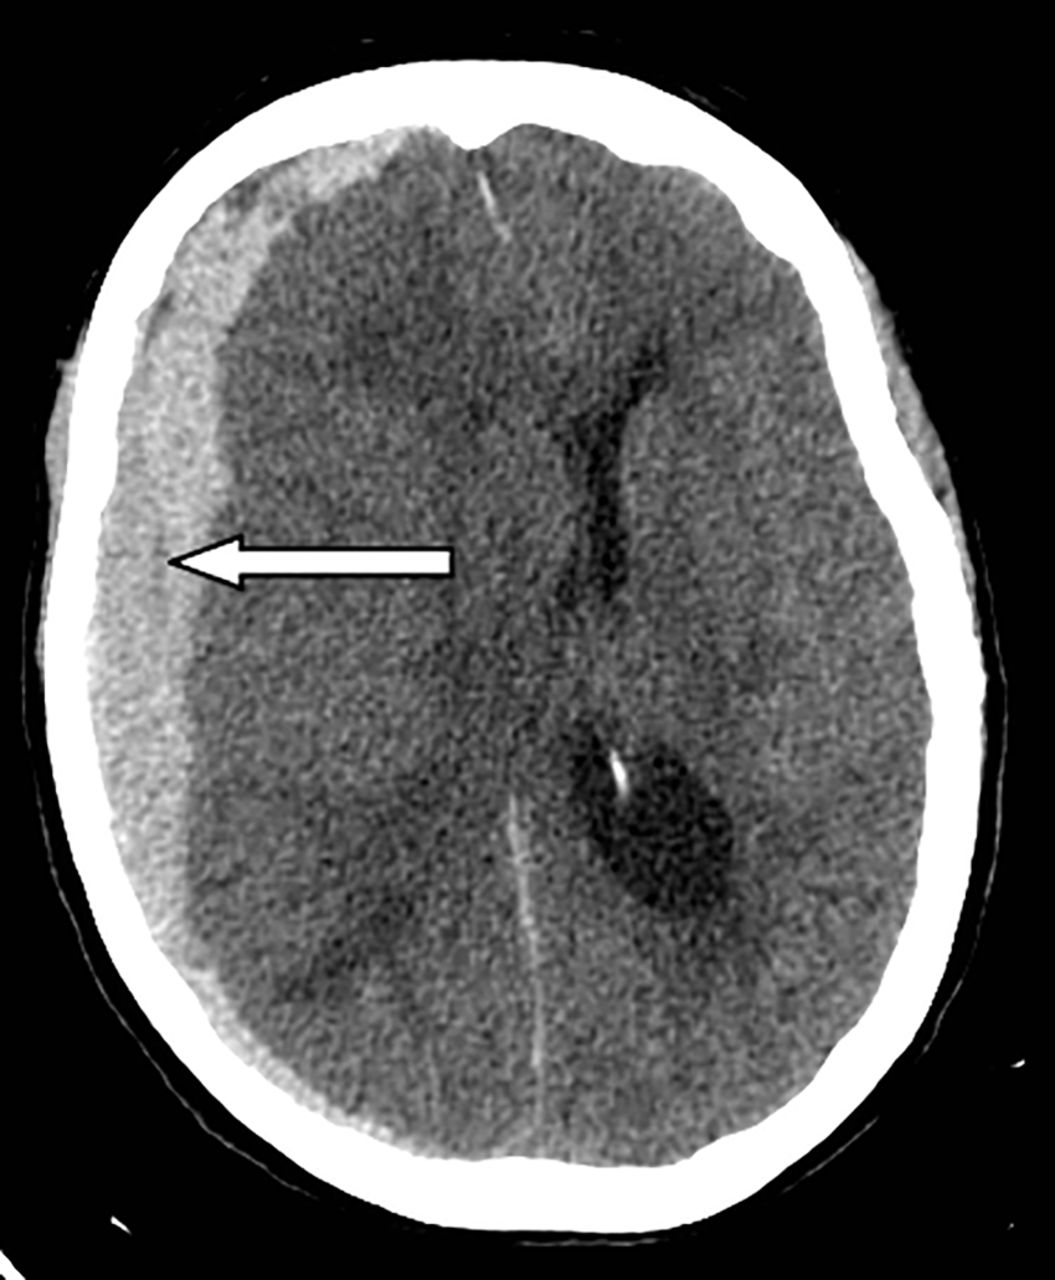

- Midline shift: Displacement of midline structures (falx cerebri, septum pellucidum) suggests mass effect from haemorrhage, tumour or major oedema.

- Haemorrhage: Hyperdense areas. Classify as epidural, subdural, intraparenchymal, or subarachnoid based on location and shape.

- Ventricular size: Look for dilatation, compression or asymmetry suggesting hydrocephalus, raised ICP or mass effect.

| Subdural haemorrhage | Crescent-shaped hyperdensity along brain surface, crossing suture lines, may track over a large area. Often associated with mass effect and possible midline shift. |

| Epidural haemorrhage | Biconvex (lens-shaped) hyperdensity that typically does not cross suture lines. May cause mass effect and midline shift; commonly related to skull fracture. |

| Intracerebral / intraparenchymal haemorrhage | Hyperdense collection within brain parenchyma with variable mass effect. Appearance depends on location and size; may extend into ventricles. |